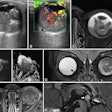

Secondly, speakers described how elastography can permit rapid assessment of liver fibrosis that seems free of adverse events, is comfortable for the patient and sonographer, and has a mean duration of around five minutes. Click here to learn more.